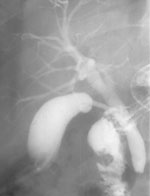

3. Больной М., 58 лет, находился в хирургии с механической желтухой, обусловленной

наличием конкремента в терминальном отделе общего желчного протока. С целью

разгрузки желчных путей была установлена дренажная трубка в желчном пузыре.

Врачами было предложено извлечение конкремента с помощью фибродуоденоскопа через

сфинктер Одди. Предварительно была произведена чрезпузырная холлангиография

с водорастворимым контрастным веществом и релаксационная дуоденография с барием

с целью уточнения локализации конкремента. На произведенной рентгенограмме конкремент

расположен в 2 см от сфинктера Одди. Полученная информация изменила тактику

лечения (Рис. 3).

Рис. 3. При заполнении желчных протоков определяется обтурация

желчного протока конкрементом (Слева). При контрастировании

желудка и 12-перстной кишки определено расстояние между уровнем

обтурации и сфинктером Одди (Справа).